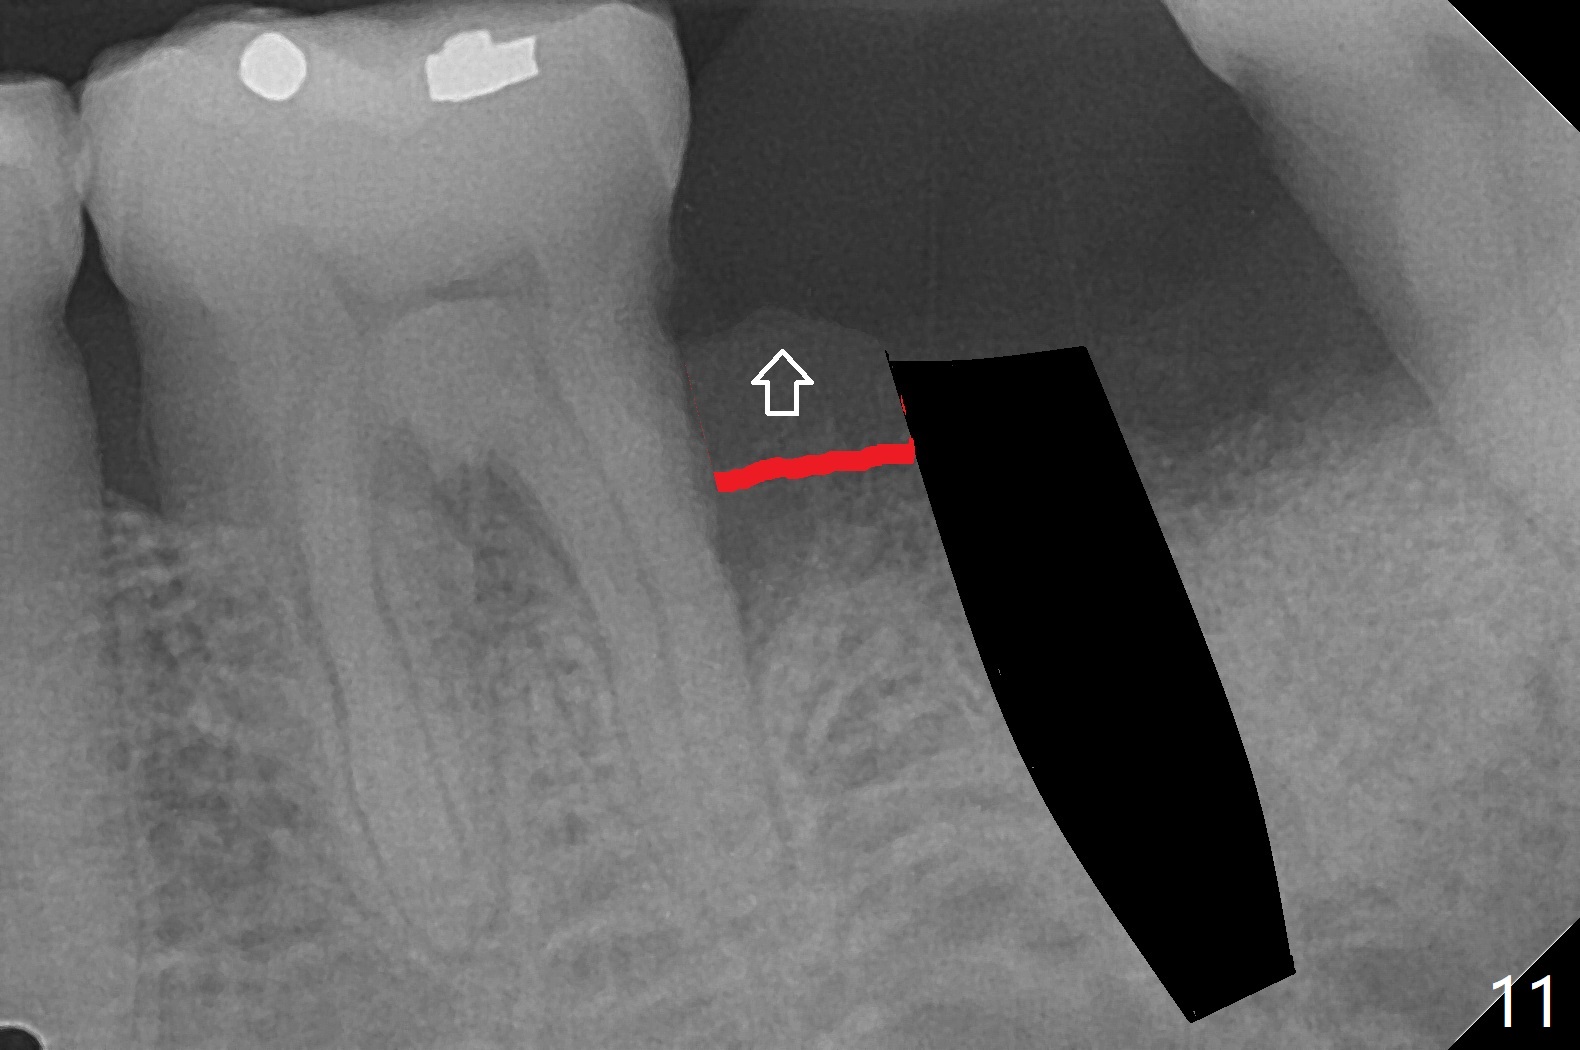

完成钻洞后(图十),潜行分离(掀开)近中牙龈(图十一),去除6远中肉芽组织和结石(图十二),涂Endogain,放置粘性骨粉(图十三),最后放置植体。